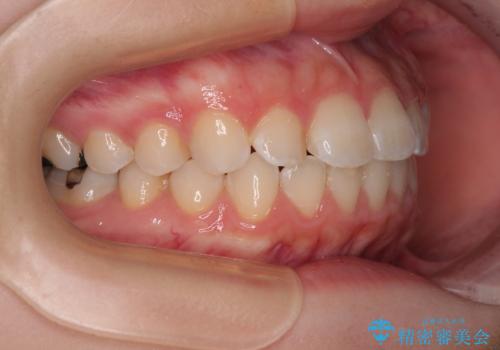

- 上下前歯部のデコボコを気にして来院された患者様です。

叢生は軽度であったため、マウスピースでもワイヤー装置でも対応可能でしたが、マウスピースを長時間使用する自信がないとのことでワイヤー装置にて矯正治療を行うこととしました。

叢生が軽度であったため、僅か半年で装置を除去することができました。